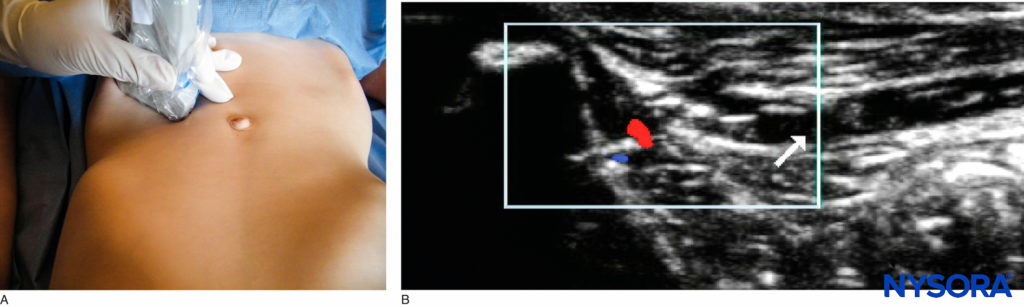

Ultrasound-Guided Technique The probe is placed on a line from the anterior superior iliac spine to the umbilicus, with the lateral end of the probe resting on the bone (Figures 11). With practice, the nerves can be tracked more proximally toward the midaxillary line, which prevents the local anesthetic spreading too far into the surgeon’s field and disrupting their tissue planes. Experts in this field have managed to successfully block these nerves with a volume of local anesthetic as little as 0.075 mL/kg.

FIGURE 11. Ilioinguinal/iliohypogastric nerve block: (A) probe position; (B) US image.

Complications An ilioinguinal/iliohypogastric nerve block is relatively safe. Perforation of the bowel wall can occur, however, and has been reported. Femoral nerve block may occur in up to 11% of cases; therefore, all ambulant children should be tested for weight bearing prior to discharge.